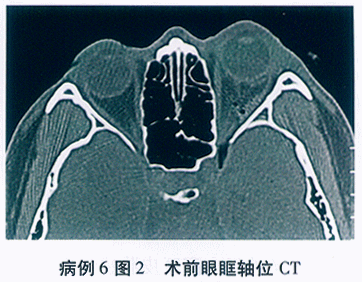

(4)CT检查:

肺纹理增双多,右肺上叶见小片状模糊影, 右肺门结构增大,胸膜增厚, 少许胸腔积液双侧肾上部见增大肿块,约6.1X8.9cm左侧胰尾区见肿块, 约5.3X7.3cm,密度不均